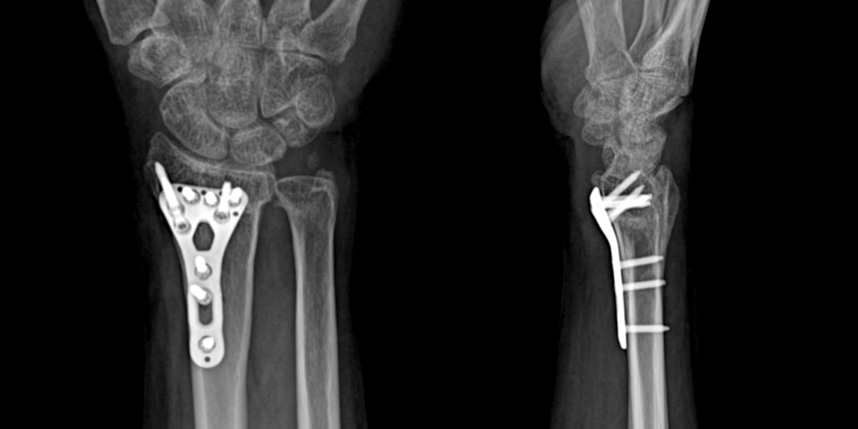

골절이 심하지 않은 경우에는 깁스로 고정해서 유합을 시킬 수 있으나, 정도가 심한 경우에는 손,발목 골절 수술을 진행할 수 있습니다.

골절은 정확하게 골절편을 잘 맞추고 고정하는 것이 중요합니다. 특히 관절면을 잘 맞추는 것이 중요합니다.

손목 골절